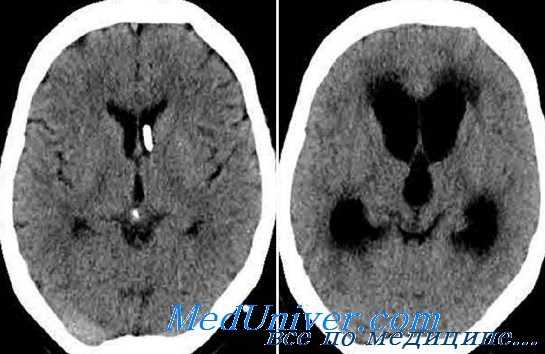

Ведущим методом диагностики хронической дизрезорбтивной гидроцефалии является КТ головного мозга. Патогномоничными признаками хронической дизрезорбтивной гидроцефалии по данным КТ являются:

1. Симметричное расширение желудочковой системы головного мозга с преимущественным баллонообразным расширением передних рогов боковых желудочков, исчезновение «талии» у передних рогов. Степень расширения желудочковой системы определяют путем расчета вентрикулокраниальных индексов (ВКИ) по общепринятой методике.

Вентркуолокраниальный индекс (ВКИ) 1 рассчитывают как отношение расстояния между самыми латеральными участками передних рогов к максимальному расстоянию между внутренними пластинками костей черепа. Верхняя граница для ВКИ 1 улиц моложе 60 лет составляет 26,4%; старше 60 лет — 29,4%.

Вентркуолокраниальный индекс (ВКИ) 2 вычисляют как отношение ширины боковых желудочков на уровне головок хвостатых ядер к максимальному расстоянию между внутренними пластинками костей черепа. ВКИ2 для пациентов моложе 36 лет равен 16%; от 36 до 45 лет — 17%; от 46 до 55 лет — 18%; от 56 до 65 лет — 19%; от 66 до 75 лет — 20%; старше 76 лет — 21%.

Вентркуолокраниальный индекс (ВКИ) З определяется как отношение максимальной ширины III желудочка к наибольшему расстоянию между внутренними пластинками костей черепа. Предел нормы для ВКИЗ у людей моложе 30 лет составляет 2,7%; от 31 до 40 лет - 2,9%; от 41 до 60 лет - 3,3%; от 61 до 70 лет — 3,9%; старше 70 лет — 4,3%. ВКИ4 получают путем расчета отношения ширины IV желудочка к максимальному диаметру задней черепной ямки, а ВКИ тел — как отношение расстояния наиболее удаленных точек тел боковых желудочков к максимальному расстоянию между внутренними пластинками костей черепа. ВКИ4 является наиболее постоянным для всех возрастных групп, его верхняя граница нормы составляет 13%.

2. Появление перивентрикулярного снижения плотности мозгового вещества — перивентрикулярного лейкоареоза (ПЛ). В распространенности ПЛ выделяют 3 стадии. На первой стадии, соответствующей появлению первых симптомов заболевания, очаги ПЛ локализуются только вокруг верхушек передних рогов боковых желудочков наподобие «кисточек на ушах рыси». Во вторую стадию очаги ПЛ располагаются вокруг передних, задних и нижних рогов боковых желудочков.

И наконец, на более поздней, третьей стадии, которая соответствует далеко зашедшим случаям дизрезорбтивной гидроцефалии, обширные очаги ПЛ прилегают ко всем участкам желудочковой системы (передние рога, тела, задние и нижние рога боковых желудочков, перивентрикулярная область III и IV желудочков).

3. Сужение и отсутствие визуализации субарахноидальных щелей головного мозга.